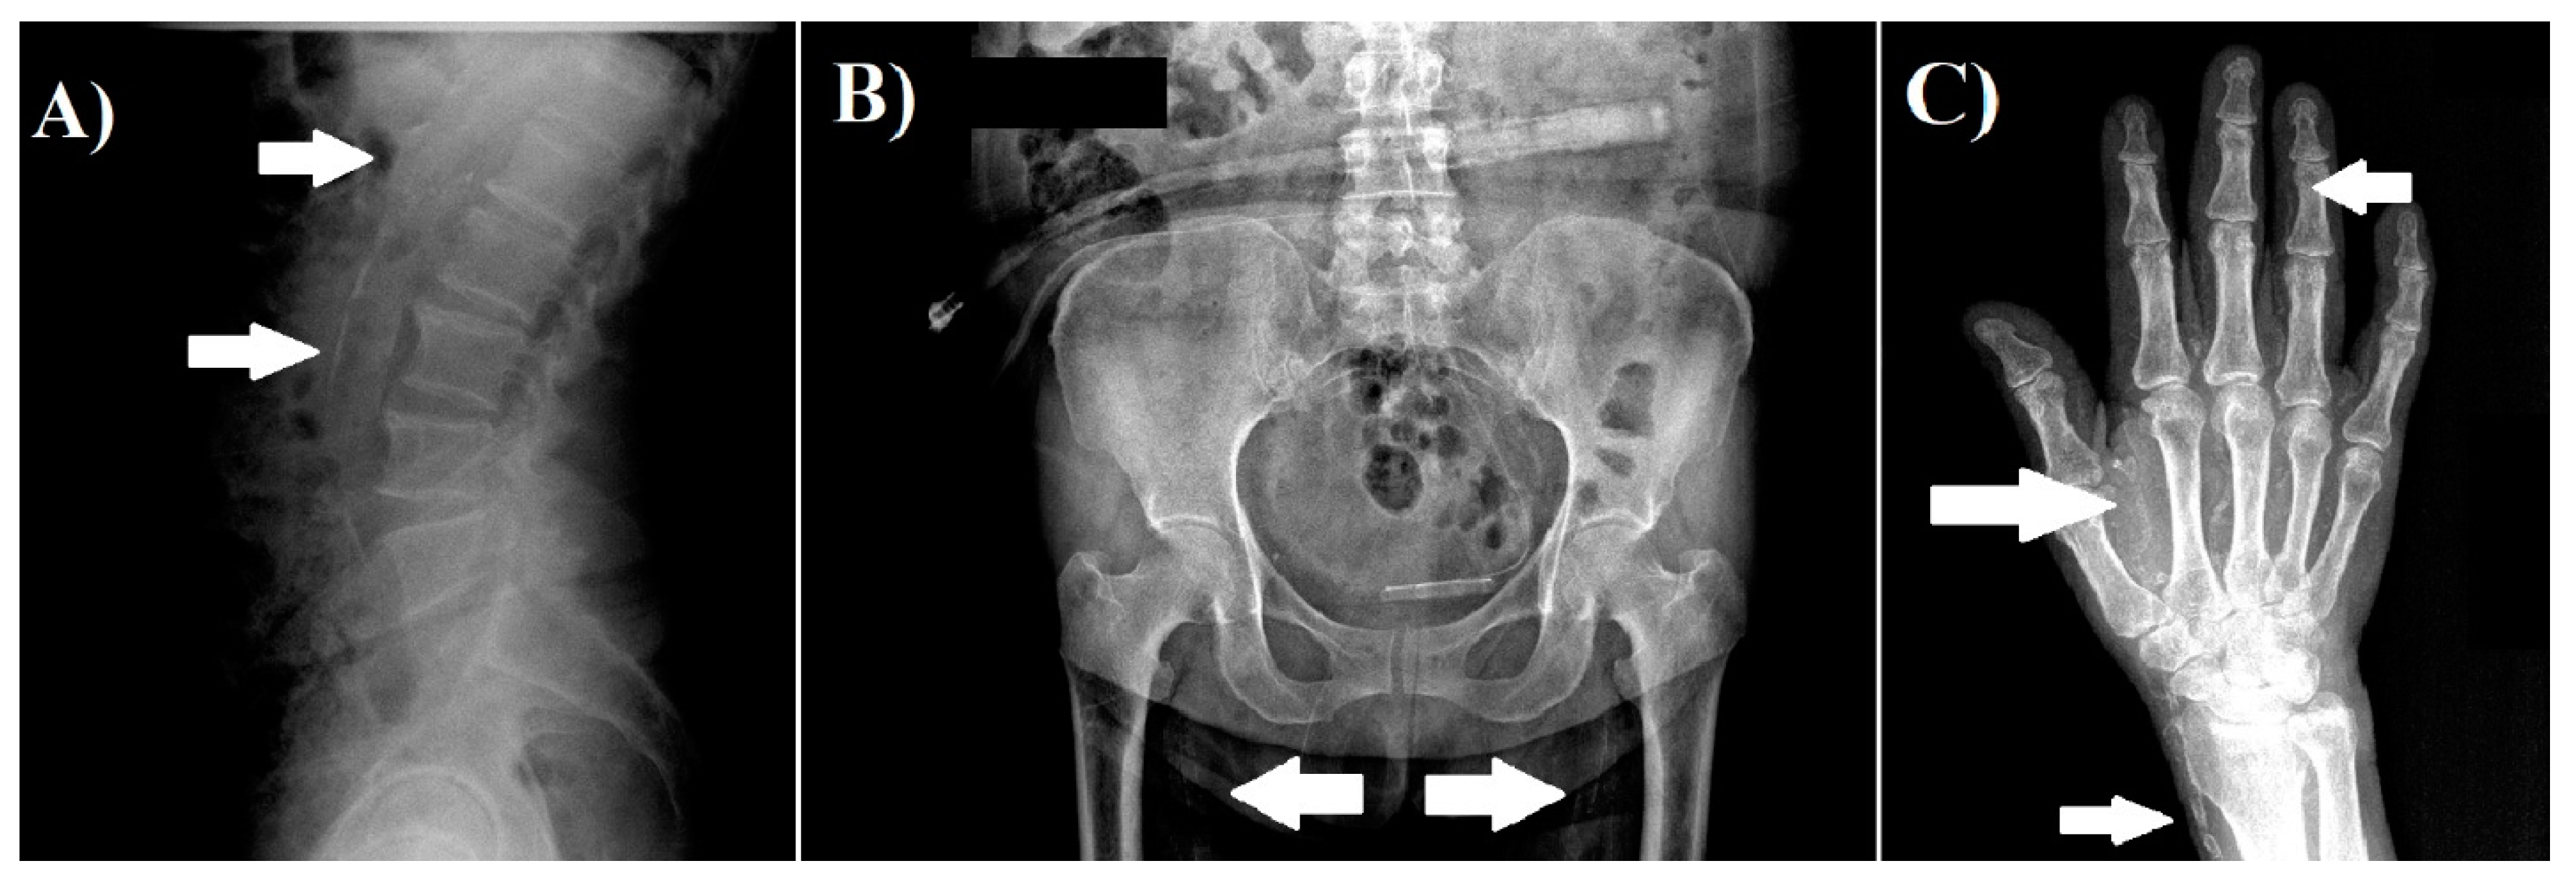

2.3. Vascular Calcification Assessment

- Gan, L.Y.; Wang, M.; Yu, X.Y. Application of plain radiography for diagnosis of vascular calcification in maintenance hemodialysis patients. Chin. J. Nephrol. 2009, 2, 81–85. [Google Scholar]